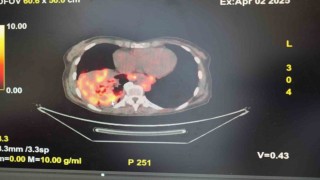

Sigarasız akciğer kanseri vakalarında dikkat çeken artış Önceki Haber

Sigarasız akciğer kanseri vakalarında di...